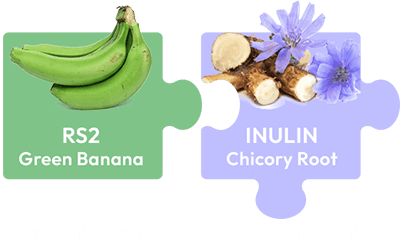

One ingredient stood out: potato starch.

Unlike bananas, potato starch holds their RS2 levels for years ... when processed correctly.

He also found another compound called chicory root.

Which contains something called Inulin.

Which amplifies the benefits of RS2.

A 2024 meta-analysis looked at 32 studies with over 1,100 people.

The results were just as shocking.

People who added chicory root lost 300% more belly fat than those who didn't.

Even when their diets stayed exactly the same.

Pharmaceutical-grade RS2 from premium potato starch that feeds your gut's butyrate-producing bacteria

Concentrated chicory root with verified inulin content that amplifies butyrate production by up to 300%